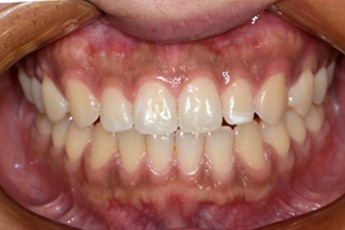

Before

After